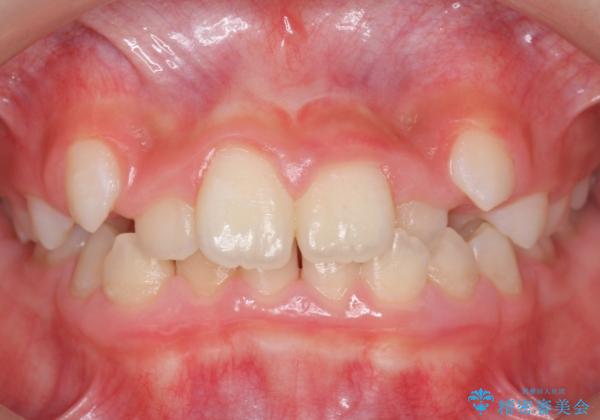

八重歯 歯を抜かずにインビザラインで

- 八重歯を主訴に来院。

抜かずに歯を少し削って入れる方法で並べました。

10代のうちに矯正をしておくと歯の移動は簡単で、歯ぐきも下がりにくいです。

可能なら低年齢のうちに矯正をするのがお勧めです。